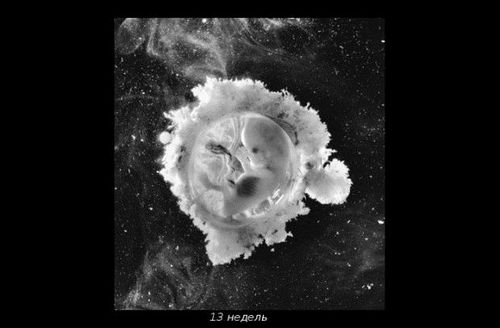

Відкрити завісу таємниці зміг шведський фотограф Леннарт Нільсон. Протягом 10 років він знімав, як розвивається ембріон від моменту зачаття і до народження. Подивитися його роботи ви можете нижче.

У 1965-му році Нільсон видав фотокнигу «A Child is Born», яка до сих пір залишається однією з найбільш продаваних.

До 8-ми тижнів, поки не сформуються більшість органів, ваш малюк буде називатися ембріоном, а пізніше - плодом.